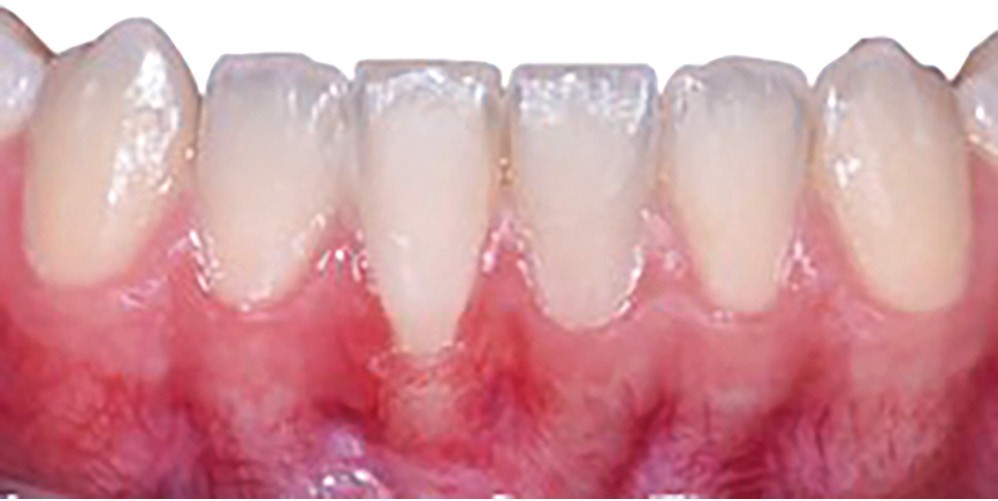

La récession RT1 est une récession sans perte d’attache interproximale et où la JAC est cliniquement non détectable en zone interproximale, le recouvrement complet est possible. Lorsque la perte d’attache interproximale est inférieure ou égale à la perte d’attache vestibulaire, on parlera de récessions RT2, le recouvrement ne sera que partiel. La récession RT3 est une récession où la perte d’attache interproximale est supérieure à la perte d’attache vestibulaire, dans ce cas-là le recouvrement est impossible. Il est important aussi de savoir identifier et distinguer la récession gingivale de l’éruption passive incomplète qui est une anomalie de développement de l’éruption dentaire (fig. 1).

La greffe épithélio-conjonctive (GEC) [7, 8] consiste au remplacement du tissu parodontal existant par un greffon épithélio-conjonctif dont l’indication principale est l’augmentation en hauteur et en épaisseur du tissu kératinisé (fig. 2). Elle peut aussi être utilisée dans le recouvrement radiculaire (avec des résultats en termes de recouvrement inférieurs à ceux des techniques de greffe de conjonctif enfouie), l’aménagement des crêtes édentées, l’aménagement péri-implantaires [9, 10] (fig. 3), ou en association avec un traitement ortho-parodontal [11]. Le principal défaut de cette technique est son aspect inesthétique ; elle sera donc réservée à des zones non visibles comme les incisives mandibulaires ou les zones postérieures.